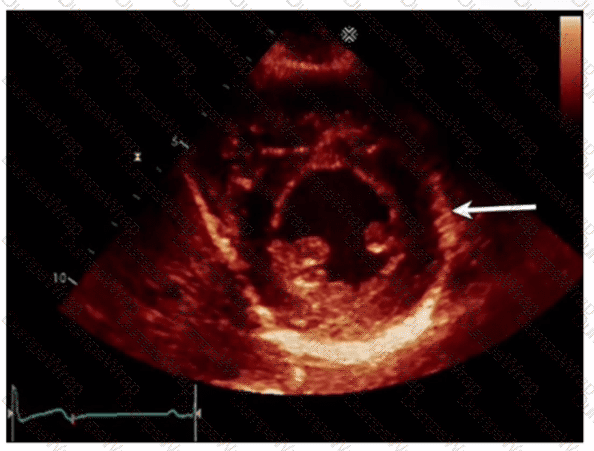

Which left ventricular regional wall segment is indicated by the arrow on this image?

CExplanation:

Comprehensive and Detailed Explanation From Exact Extract:

The echocardiographic image shows a short-axis view of the left ventricle at the mid-papillary muscle level with segmental strain values. The arrow points to the wall segment located inferiorly (towards the bottom of the image in standard orientation), which corresponds to the inferior wall of the left ventricle.

According to the standardized 17-segment model endorsed by the American Society of Echocardiography (ASE), the inferior wall is situated posteriorly and inferiorly in the short-axis view. The other options represent adjacent walls: anterior is opposite the inferior wall, anterolateral and inferolateral correspond to lateral wall segments.

This segmental anatomy and nomenclature are detailed in adult echocardiography textbooks and ASE chamber quantification guidelines, which emphasize precise segmental identification for accurate regional function assessment【12:ASE Chamber Quantification Guidelines†p.90-95】【16:Textbook of Clinical Echocardiography, 6e†p.140-145】.